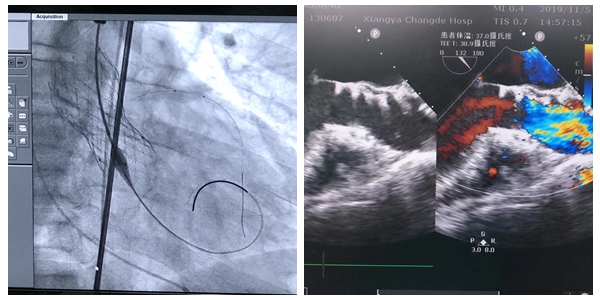

通过周密的术前准备,11月5日中午,TAVI团队在心脏介入室为刘叔叔实施了微创介入经股动脉主动脉瓣置入术(TAVI),折叠的人工主动脉瓣经过细小的管状输送系统经过心尖,精确到达主动脉瓣,瓣膜支架慢慢张开……仅一个小时的手术时间,让这位主动脉瓣狭窄并关闭不全的患者获得了“心生”。术中各项生命体征平稳,术后第二天便已下地自主行走。

复查其造影瓣膜位置良好,经食道心脏超声主动脉瓣未见返流,冠状动脉血流状况良好。